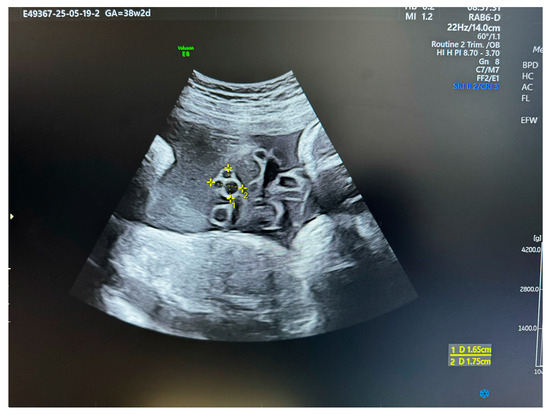

Figure 2.

US section image of a normal umbilical cord at 38 weeks of gestation.